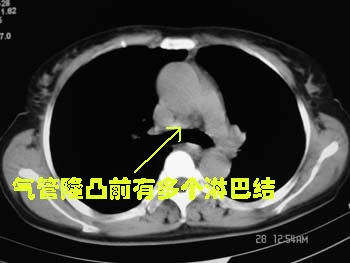

标题: CT2875:左下肺占位,请分析。

女,56y,左下肋缘下痛疼二月余

属典型的左下肺中央型肺癌——左下分叶状肺肿块、支气管阻断、左下肺不张,纵隔淋巴结肿大。

左下肺团块状软组织密度影,呈分叶状,边界清,未见小毛刺,左下肺支气管阻塞,纵隔见肿大淋巴结,考虑左下肺中央型肺癌伴纵隔淋巴结肿大,建议支纤镜检查。